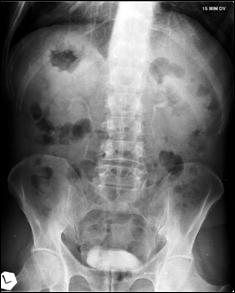

4.1. Radiografia renovezicala simpla si UIV raman examenele de baza pentru diagnosticul etiologic al oricarui pacient cu hematurie. Tumorile vezicale au drept semn radiologic cardinal imaginea lacunara pe cistograma urografica. Tumorile infiltrative pot induce modificari ale supletii peretelui vezical, care devine rigid, inextensibil, retractat etc. in zonele patologice. Ureterohidronefroza sau rinichiul mut sunt rezultatele invaziei si obstructiei ureterelor intramurale induse de tumorile solide, infiltrative (Fig.27,28,29).

Figura 33. a) Imagine lacunara voluminoasa, ocupand

hemivezica dreapta; rinichi drept mut UIV; b) Imagine lacunara in hemivezica

dreapta; c) Rigiditate la

nivelul hemivezicii drepte; d) Cistouretrografie intramictionala

demonstrand imagine lacunara in hemivezica stanga.